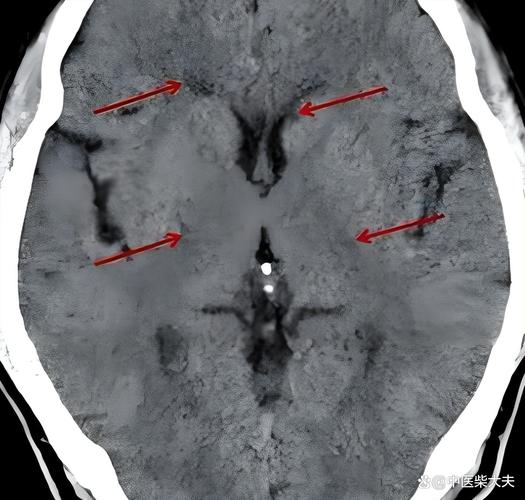

- 分水岭梗死:

- 定义: 发生在两条主要动脉供血区交界处的梗死。

- CT表现: 梗死灶呈线状或条带状,位于脑叶的边缘(皮质型)或深部白质(髓质型)。

- 常见原因: 全身性低血压、心输出量下降。

- (配图:一张显示大脑前、中动脉交界区线状低密度灶的CT图像)